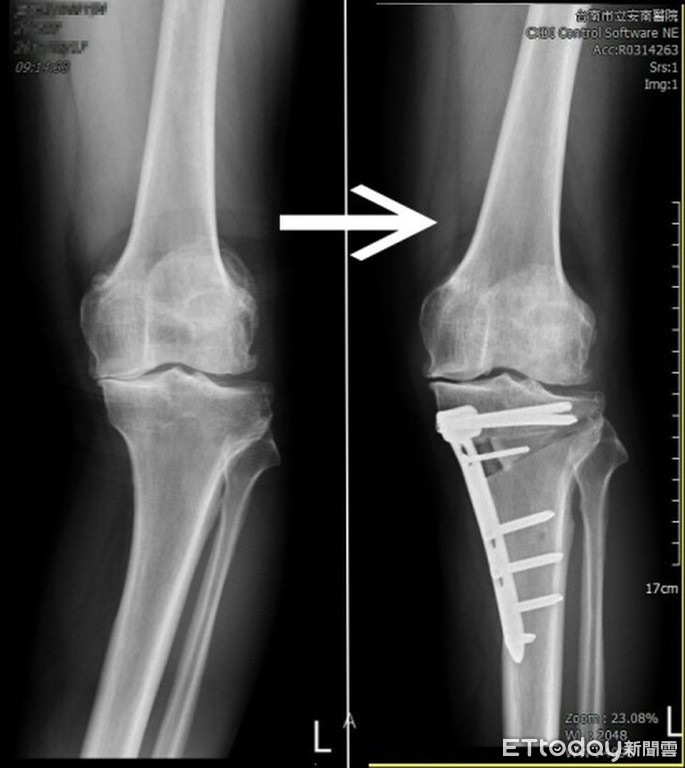

▲患者術前及術後X光影像。(圖/安南醫院提供)

其實中後期的膝關節退化,如果只有內側關節面的磨耗,不一定得接受人工關節置換,HTO高位脛骨截骨矯正術(High tibial osteotomy)也是另一個選擇。張伯羣醫師指出,HTO手術保留住所有關節面的軟骨韌帶,在關節下方開一個缺口,把一小塊骨頭補進這個缺口,最後上下兩端用鋼板固定好,把內翻矯正成直線,讓上半身的重量平均的分布在膝關節左右。